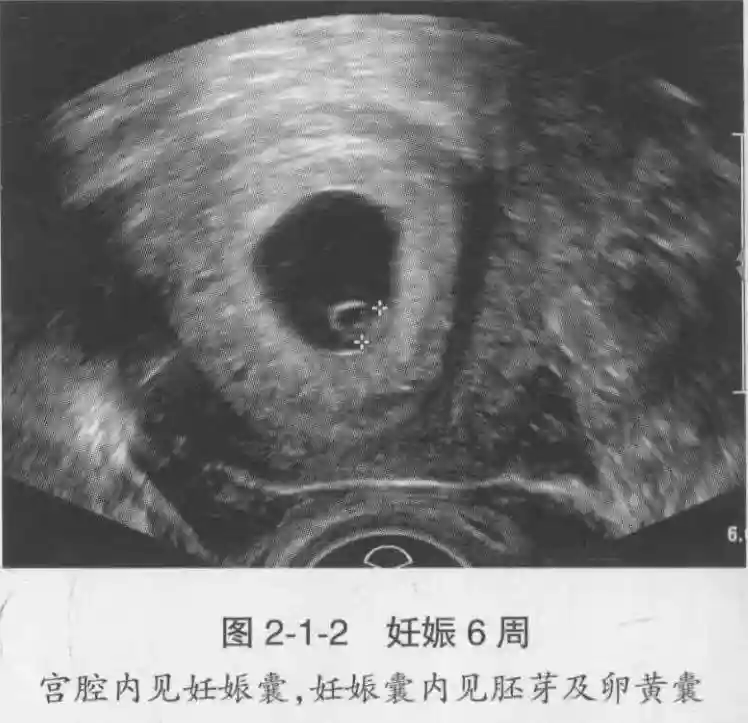

3️⃣胚胎:胚胎通常在6-7周时可以为超声显示,起初为胎芽,表现为卵黄囊一侧局部组织增厚,达到1 -2 mm 时才有可能为超声测量出来。达4-5mm时可见胎心搏动,相应孕周为6-6.5周,妊娠囊大小为13-18mm。胚芽长度≥7㎜时仍未见心管搏动,提示胚胎停止发育。胚胎的出现和妊娠囊直径的关系:妊娠囊直径> 16 mm 时,经阴道超声应显示胚胎。妊娠囊直径> 25 mm 时,经腹超声均应显示胚胎。